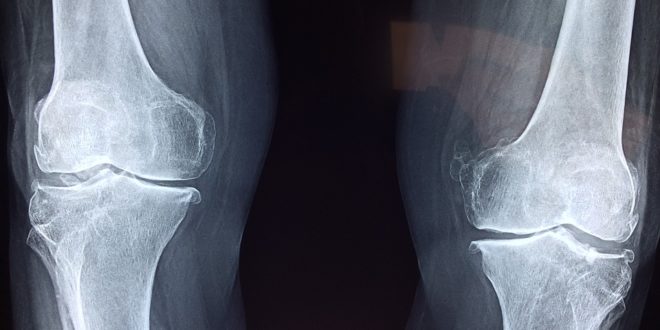

Less inflammation, healthier joints: mobility and health with less inflammation